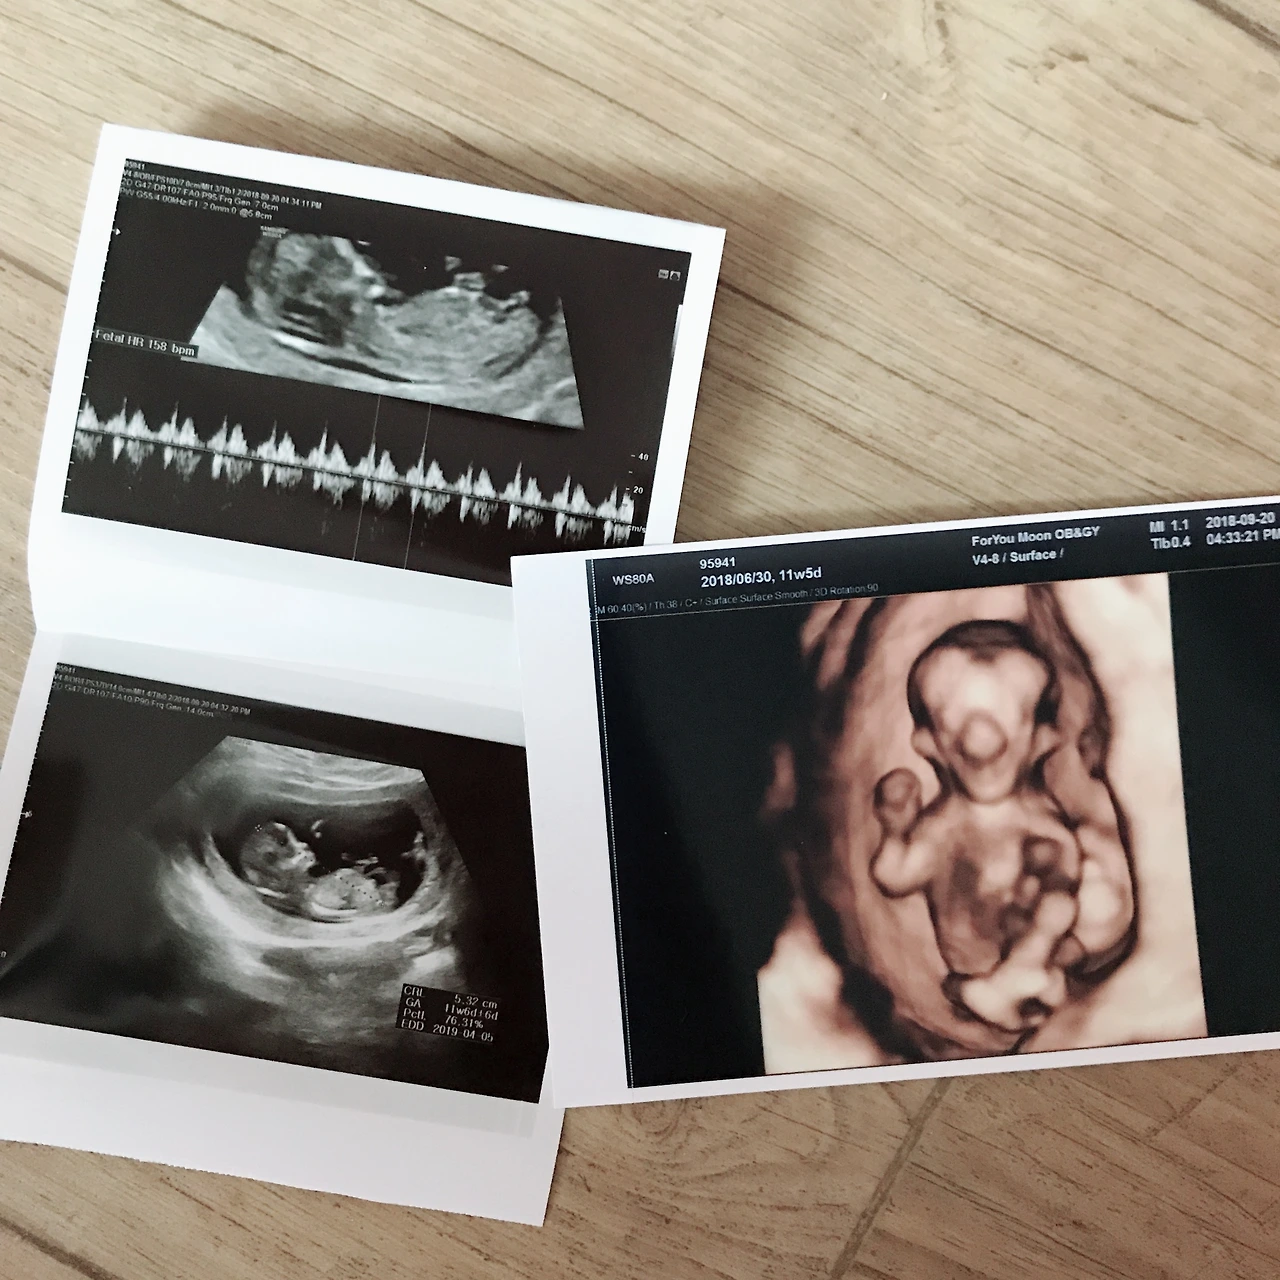

둘째 기형아 검사

어느덧 무럭무럭 자라서 새끼손가락 크기!